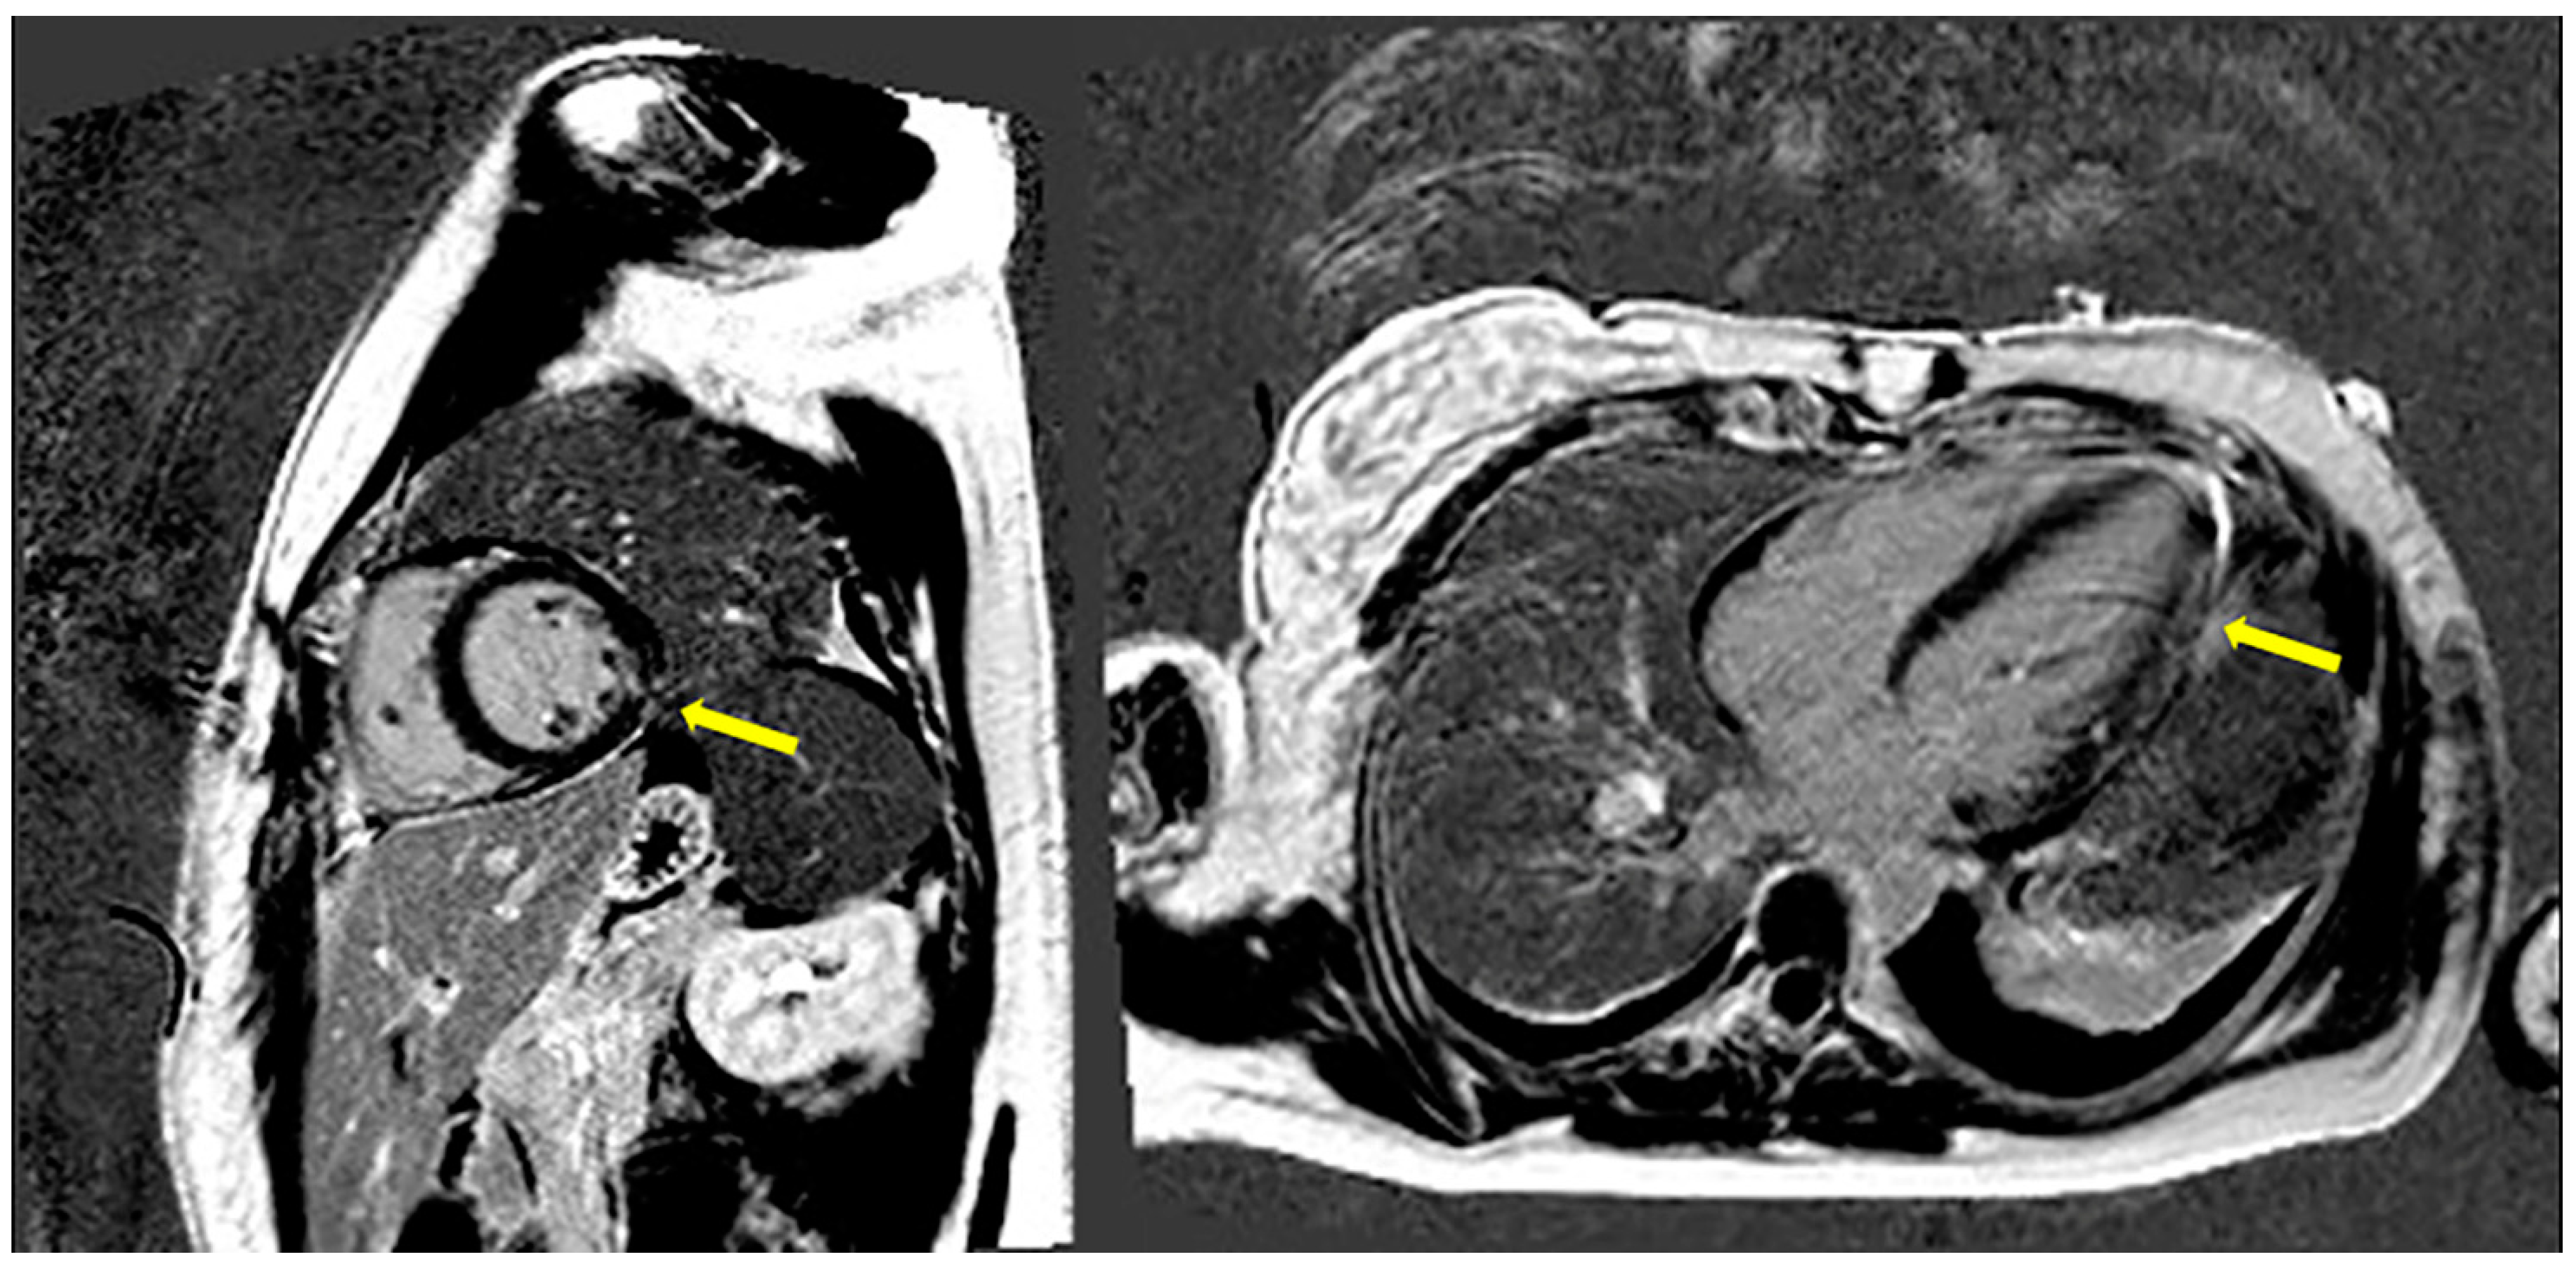

2. Case Presentation